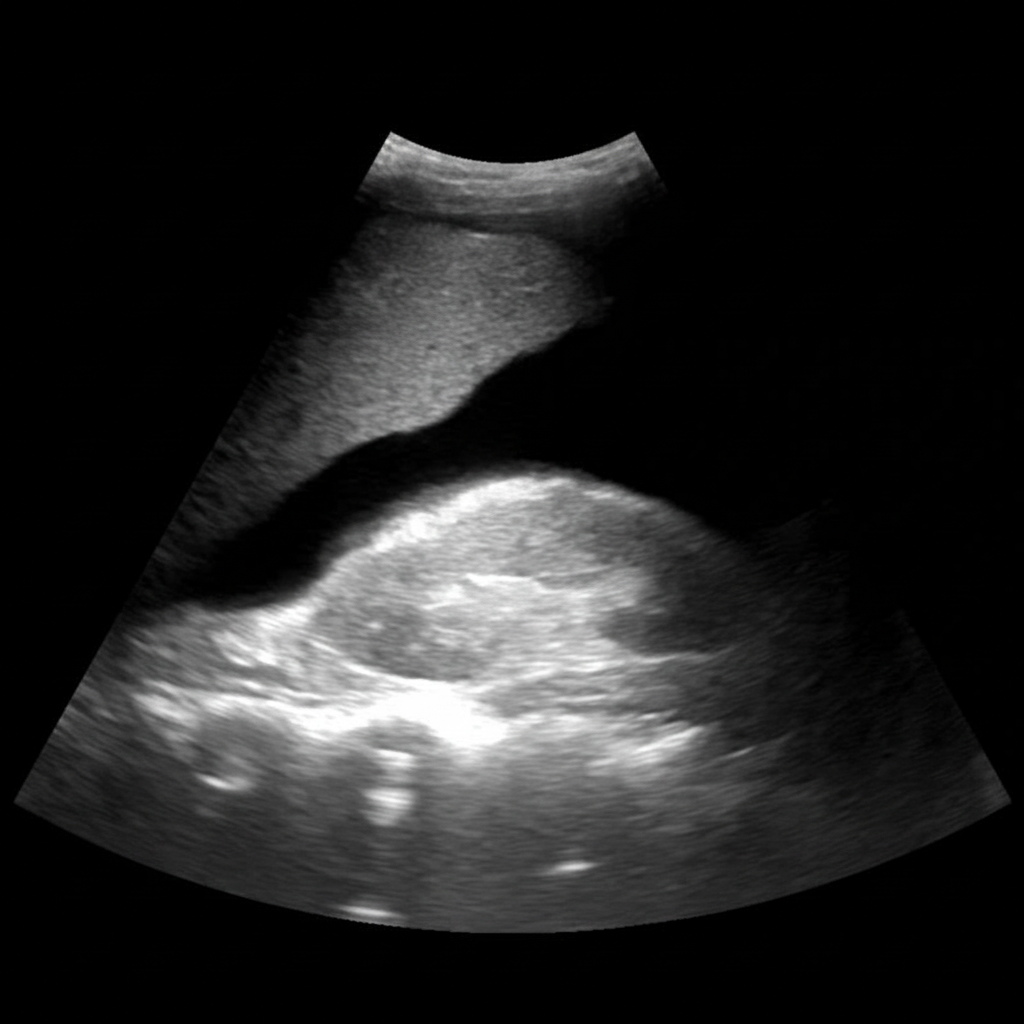

Comment on the provided ultrasound image?

Explanation: ***FAST positive*** - The ultrasound shows **free anechoic fluid** in **Morrison's pouch** (hepatorenal space), indicating **hemoperitoneum**. - A **FAST positive** result suggests significant intra-abdominal bleeding requiring immediate surgical evaluation in trauma patients. *FAST inconclusive* - This term indicates **technical difficulties** or **suboptimal visualization** preventing proper assessment of fluid collections. - Requires **repeat examination** or alternative imaging modalities like **CT scan** for definitive evaluation. *FAST negative* - A negative FAST shows **no free fluid** in any of the **four standard views** (pericardial, right upper quadrant, left upper quadrant, pelvis). - Does **not rule out** all intra-abdominal injuries, as **retroperitoneal bleeding** may not be detected. *FAST equivocal* - Refers to **borderline findings** where fluid presence is **uncertain** or **minimal amounts** are detected. - Requires **clinical correlation** and often **serial examinations** or **CT imaging** for clarification.